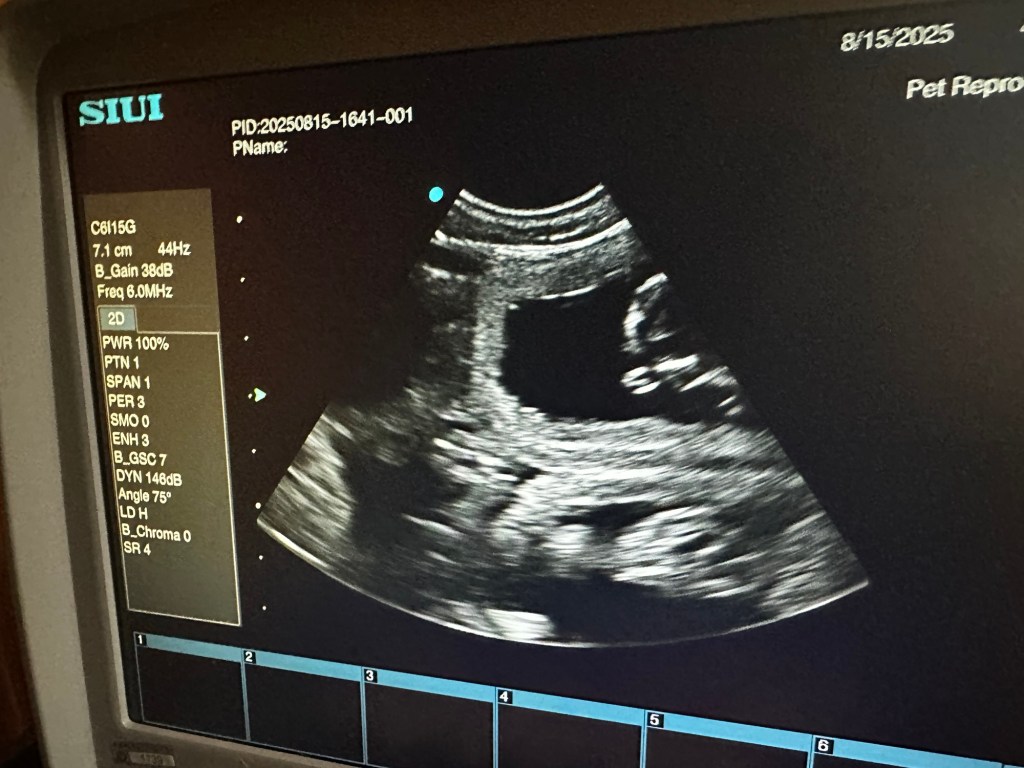

I dag har vi tatt ultralyd og begge tispene våre er drektige. Oliane med et lite kull og Naya med et stort kull. Elevene var med på ultralyd og nå er det bare å vente frem til røntgen uken før forventet termin.